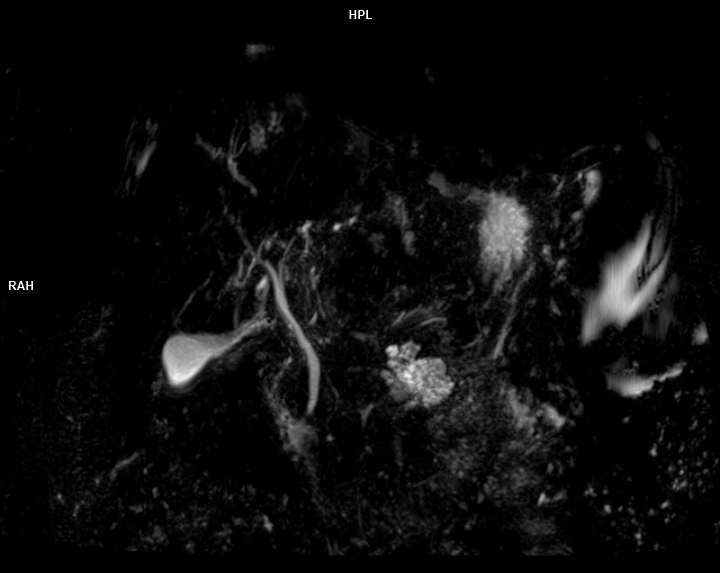

• MRCP(Kolanjiyopankreatografi)

• 3 TESLA MR ÇEKİM GÖRÜNTÜLERİ

3 Tesla MR Çekim Görüntüleri

• 3 Tesla MR Çekim Görüntüleri